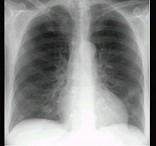

问题 68岁男性,咳嗽流涕1周入院,临床诊断为肺中叶综合征。支气管镜见多发结节状突起,从气管前壁伸入至右肺下叶支气管如图,影像检查如图。可能的诊断是 ( )

选项 A.肺结核 B.支气管肺癌 C.原发性气管支气管淀粉样变 D.肺炎 E.支气管内膜结核

答案 C